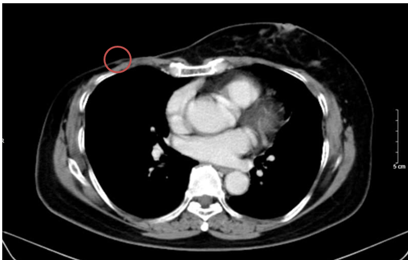

- Chụp cắt lớp vi tính bụng: Theo dõi dày khu trú tuyến thượng thận trái tạo nốt đường kính khoảng 9mm (không thay đổi)

Hình 10. Hình ảnh chụp CT bụng sau điều trị: Nốt tuyến thượng thận trái